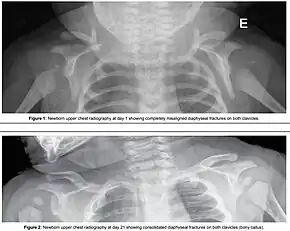

| Suprapubic pressure being used in a shoulder dystocia | |